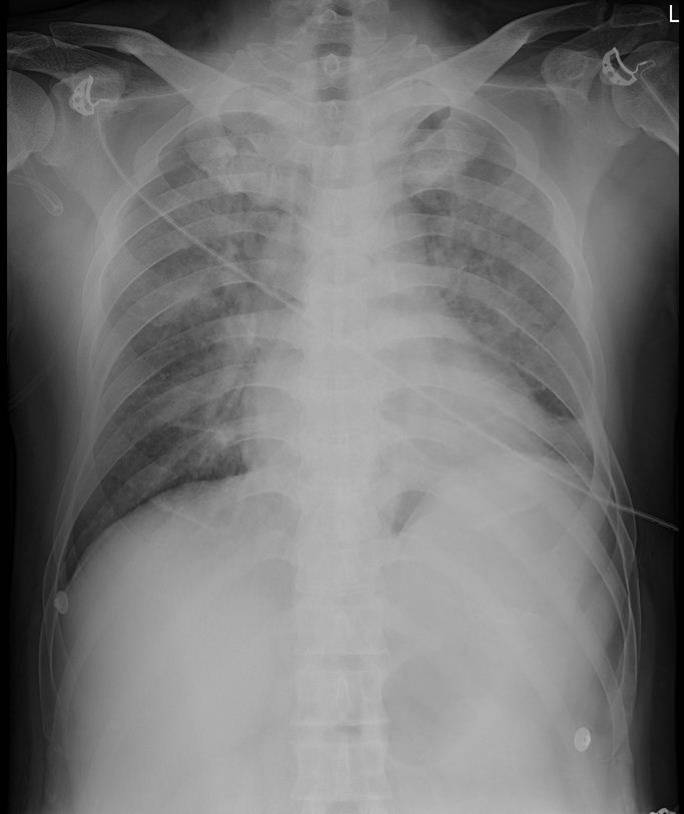

胸片(2016.11.27)

1.两肺大片状渗出影,考虑两肺肺水肿可能;

2.心影大。

胸片(2016-11-29)

◆双肺渗出,考虑肺水肿,心影大,较2016-11-27片相比,心影较前稍增大;

◆心影处可见一线样高密度影,请结合临床。